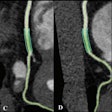

Keto diet improves PET/CT of cardiac sarcoidosis